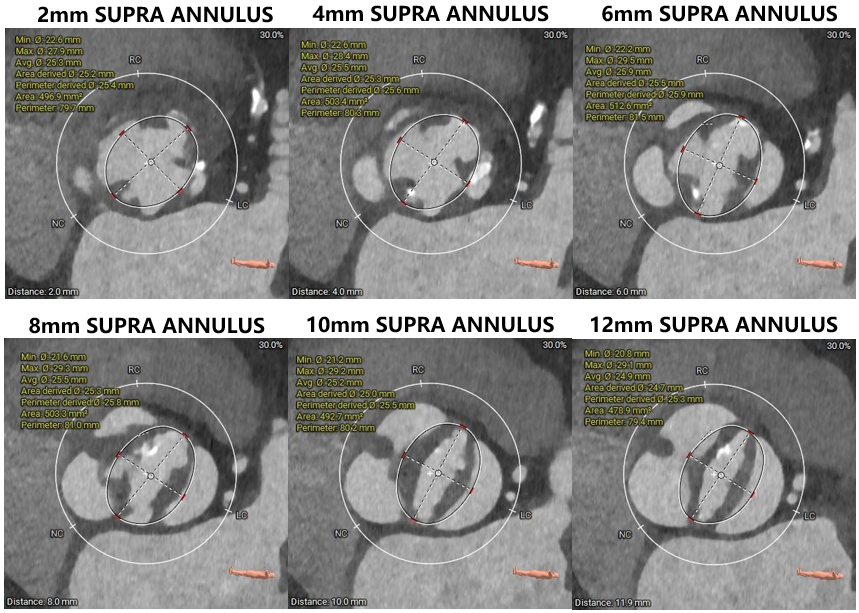

主动脉根部评估

瓣环上解剖结构评估